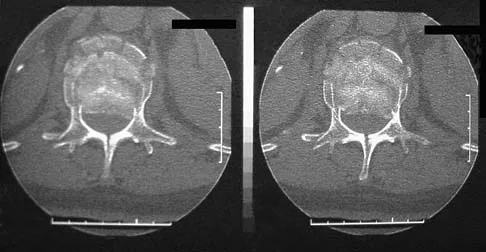

An otherwise healthy 45-year-old woman reports the onset of severe right leg pain. Figure 20a shows an axial MRI scan of the L4-5 level, and Figure 20b shows a sagittal view with the arrow at the L4-5 level. What nerve root is the most likely source of her pain?

Explanation

The scans show a disk herniation in the far lateral region of the disk. In particular, the sagittal view shows the herniation adjacent to the exiting L4 nerve root. Disk herniations in this area that cause symptoms are more likely to compress the nerve exiting at the same level rather than the next most caudal level. McCulloch JA: Microdiscectomy, in Frymoyer JW (ed): The Adult Spine: Principles and Practice. New York, NY, Raven Press, 1991, vol 2, pp 1765-1783.